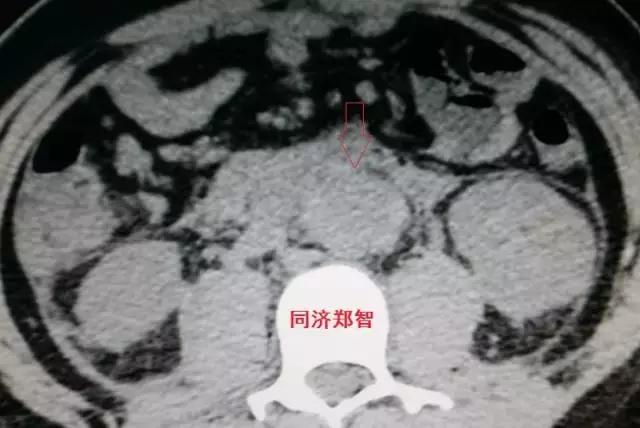

病例十

腹主动脉平扫CT提示正常外周一圈的钙化影中有内移的钙化影(红色箭头所示),CTA 证实为腹主动脉夹层。